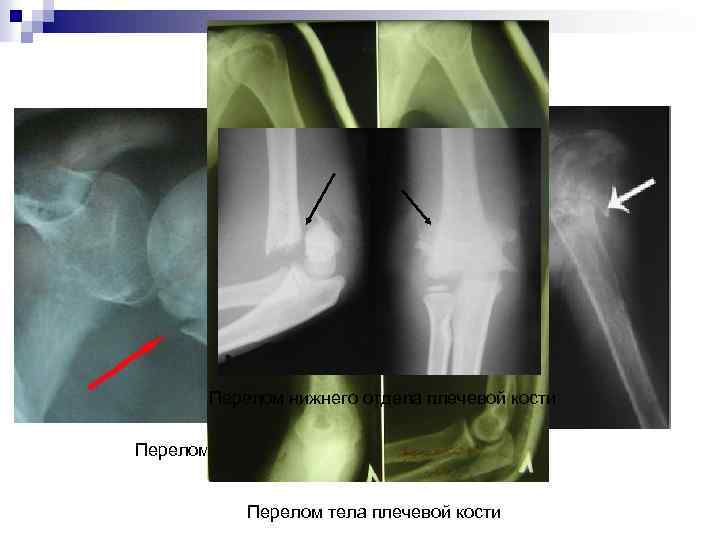

Переломы плечевой кости n Механизм перелома чаще всего непрямой. Перелом возникает при падении на выпрямленную отведенную руку, на локоть. n Диагностика внутрисуставного перелома плечевой кости: Сильные боли в суставе, резкое ограничение движений поврежденной рукой. Плечевой сустав увеличен в объеме, резко болезненный при прощупывании. При поколачивании по локтю боли появляются в месте перелома. При рентгеновском исследовании обнаруживают линию перелома. - n Ш Ш Ш Выделяют переломы плечевых костей: верхнего отдела плечевой кости: - внутрисуставные или надбугорковые - подбугорковые или внесуставные тела плечевой кости: - косые - винтообразные - поперечные - оскольчатые нижнего отдела плечевой кости: - внесуставные - внутрисуставные.

Перелом нижнего отдела плечевой кости Перелом верхнего отдела плечевой кости Перелом тела плечевой кости